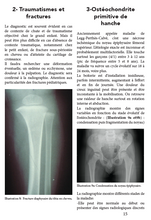

2-Traumatismes et fractures

3-Ostéochondrite primitive de hanche